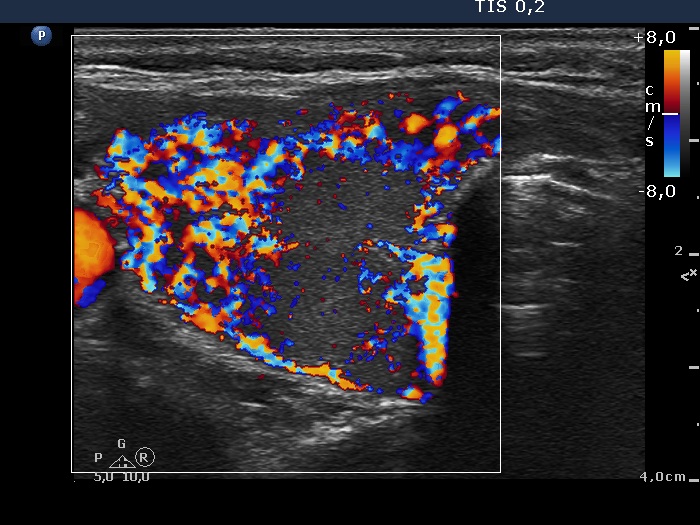

Graves' disease - case 18 (ultrasonographic picture 3)

Right lobe, longitudinal scan

Right lobe, transverse view, color Doppler mode. The vascularization is significantly increased.